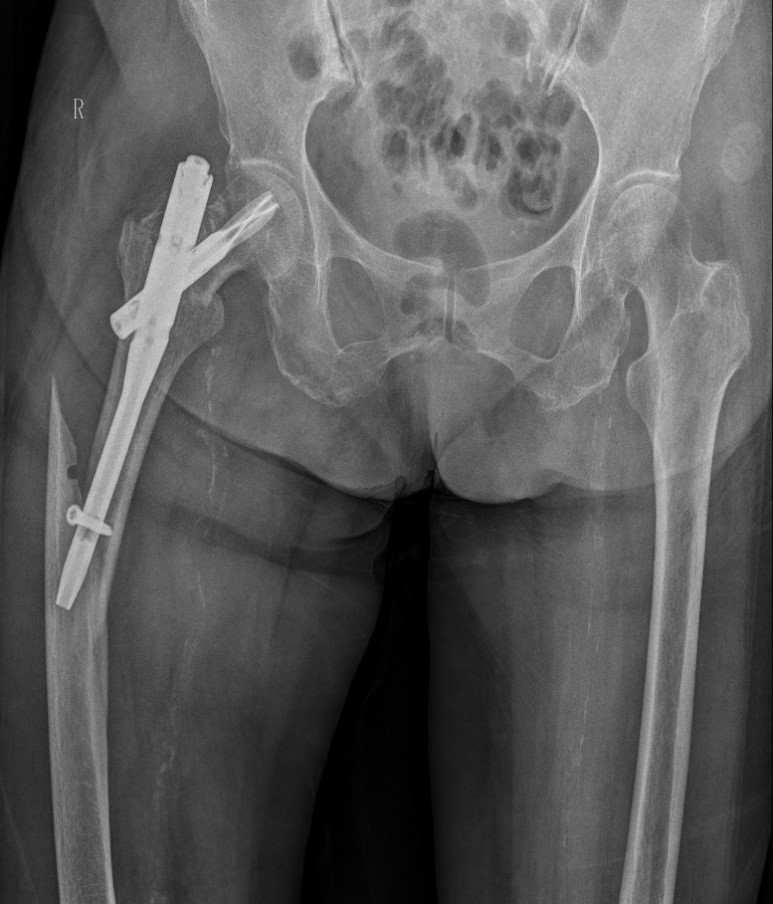

案例一:82岁女性术后再摔伤

患者情况:熊奶奶,一个月前在金瓶梅电影因右髋骨折接受髓内针内固定术,术后康复中因不慎摔倒,再次出现右髋部疼痛并活动受限。经检查,确诊为股骨骨折。患者伴有帕金森病和高血压,身体状况较差。